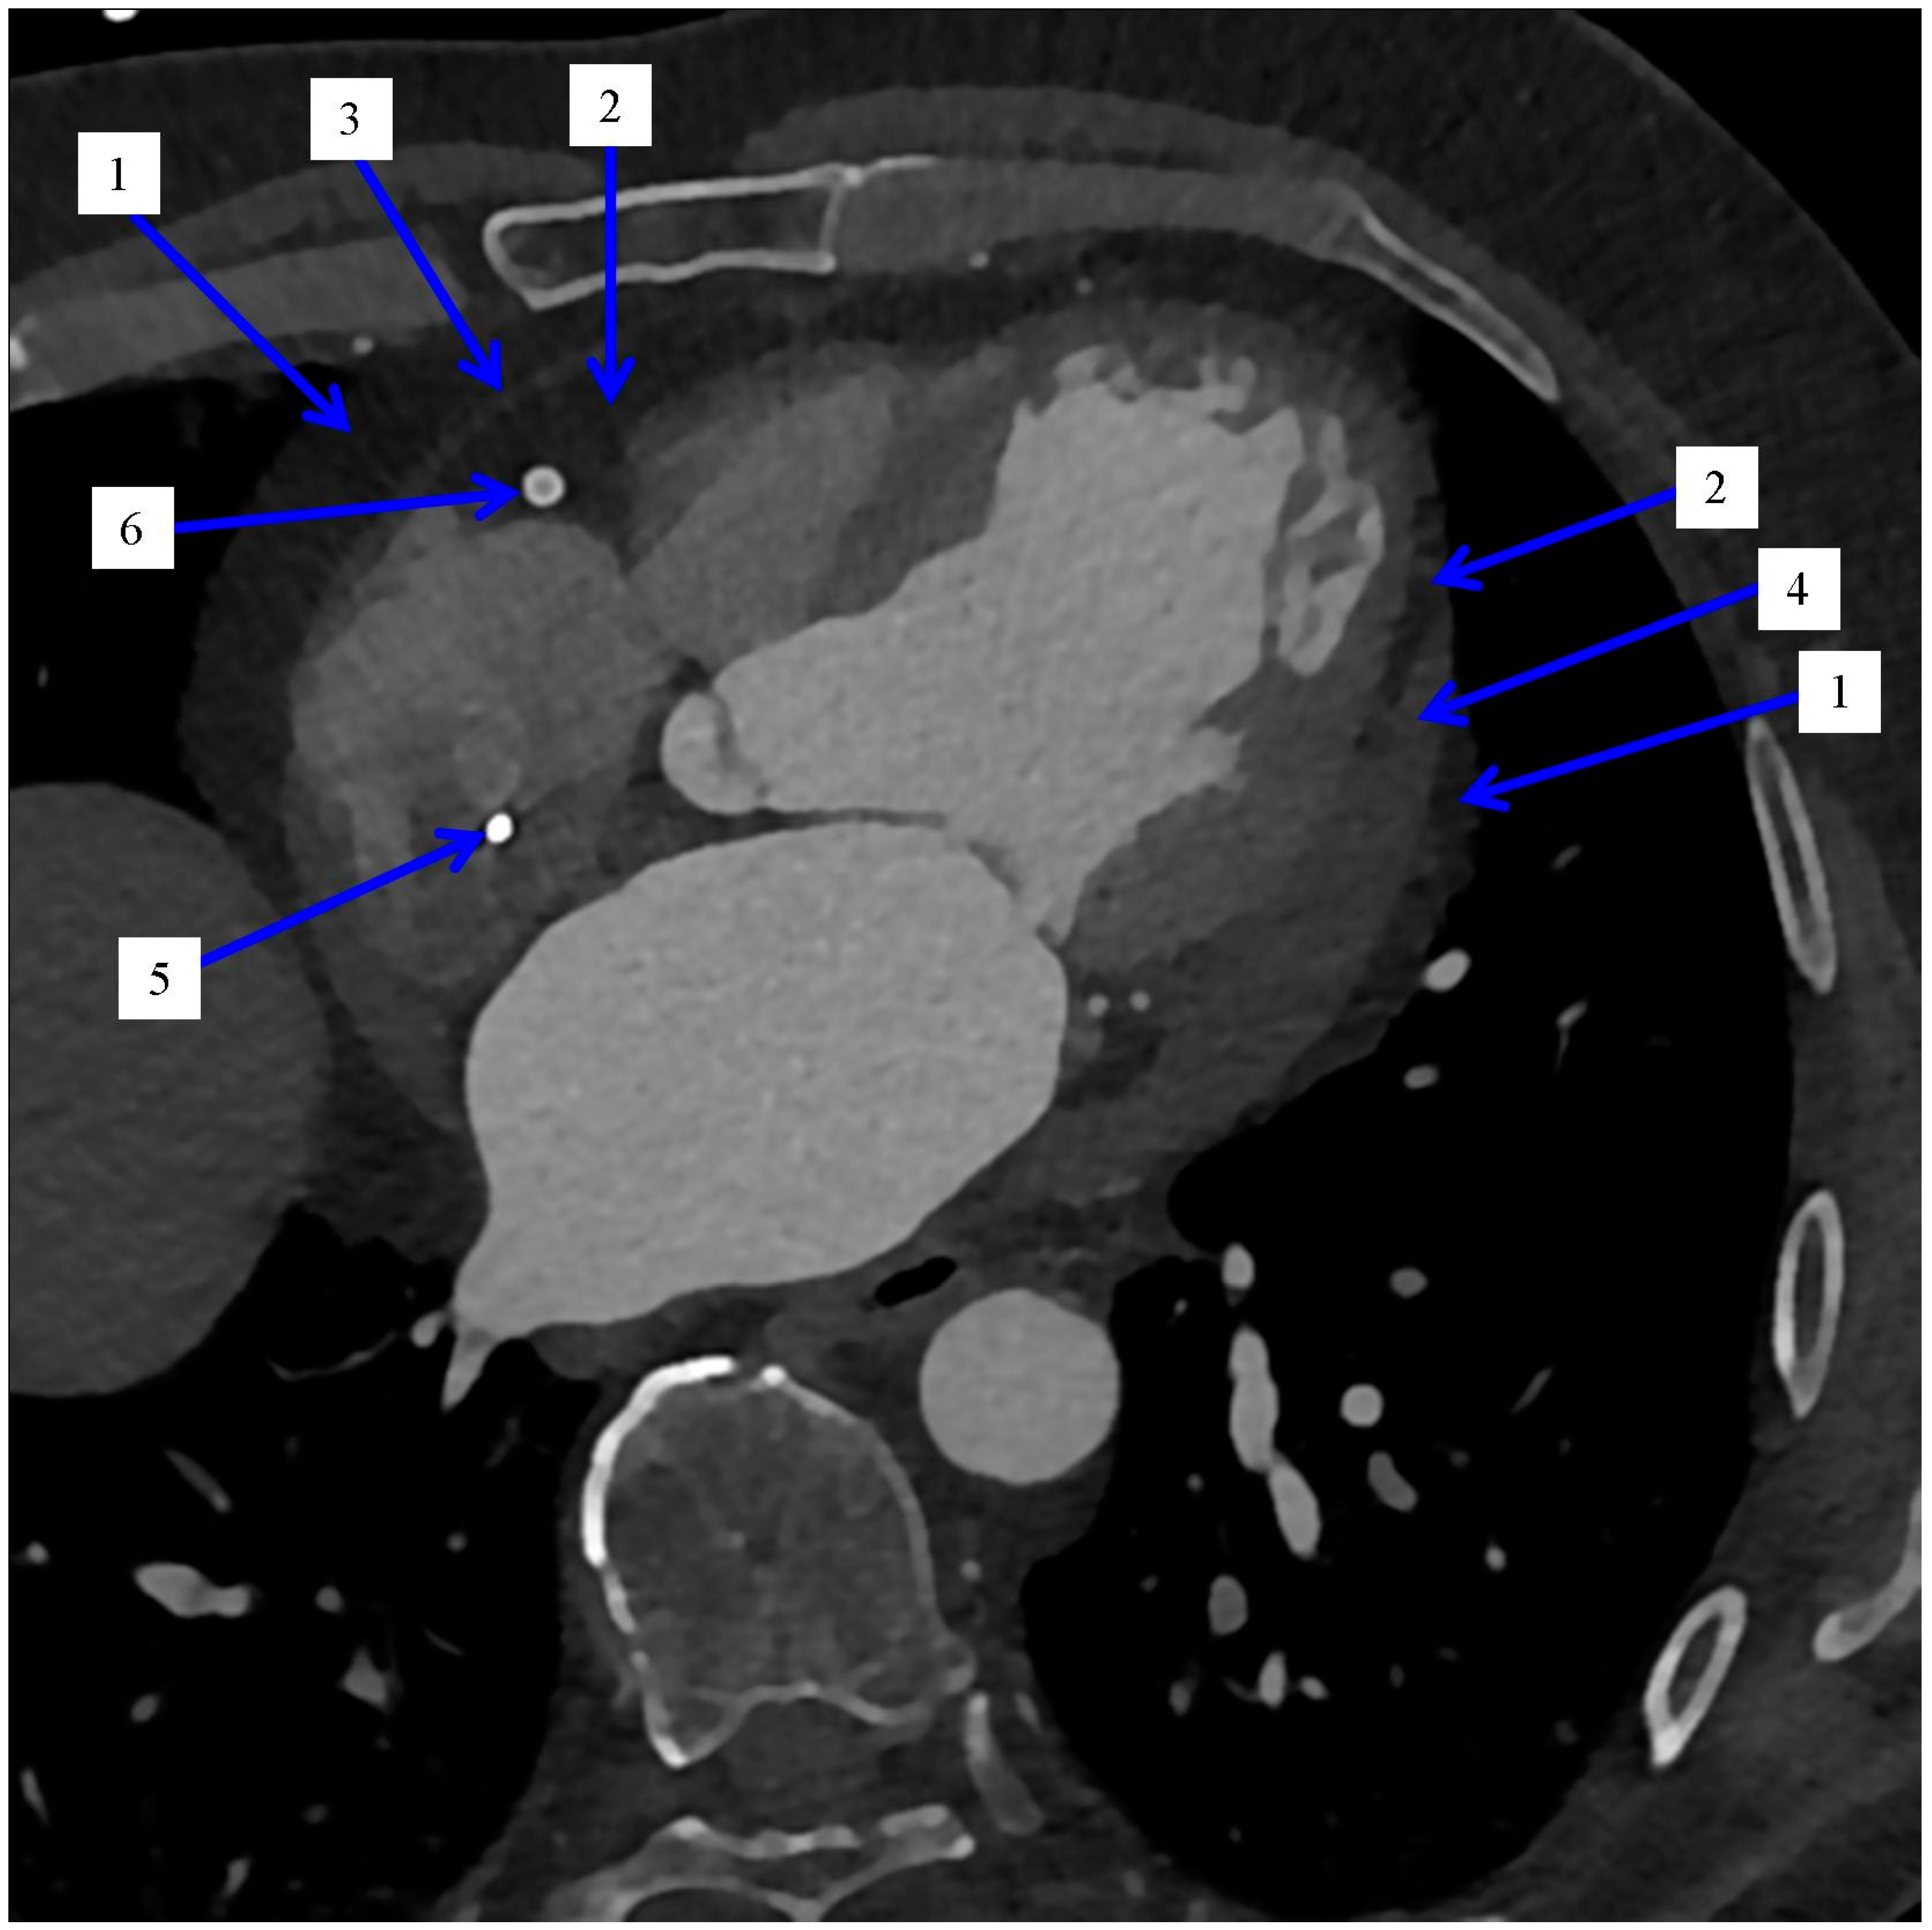

2.2. Imaging and Measurement Methods of Epicardial Adipose Tissue